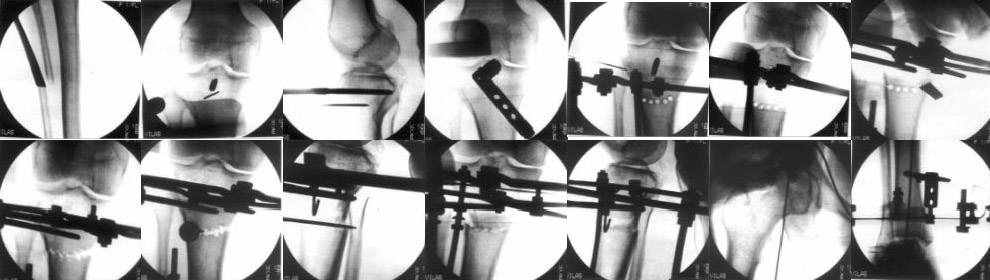

Картинки - в приложении.Будут вопросы - готов ответить.

Sending you pics of the steps of the osteotomy and the frame.

You can do the osteotomy in a "focal dome" or in a transverse fashion. The dome has the advantage of having a good contact, allowing weight bearing as tolerated early on.

The level is below the tibial tuberosity.

The frame I use is pretty simple, with one wire each in the proximal and distal ring, two schanz pins in the proximal ring, and one each in the middle and distal ring.

I preconstruct a frame with the proximal ring in varus by the use of coupled washers in the threaded rods in the front and back. These are used as hinges, and after the correction, a medial and lateral threaded rod is also added.

Since the center of rotation of these deformities is usually near the knee joint line, lateral translation of the distal fragment is necessary to normalise all the axes.

You can also do the osteotomy in a transverse fashion.

When I use an orthofix fixator, the osteotomy is oblique, starting below the tuberosity and ending 1 cm away from the lateral cortex at the level of the head of the fibula. No fibular osteotomy is needed there. The deformity is gradually corrected over 2 or three weeks.

You could also do the same with an ilizarov fixator